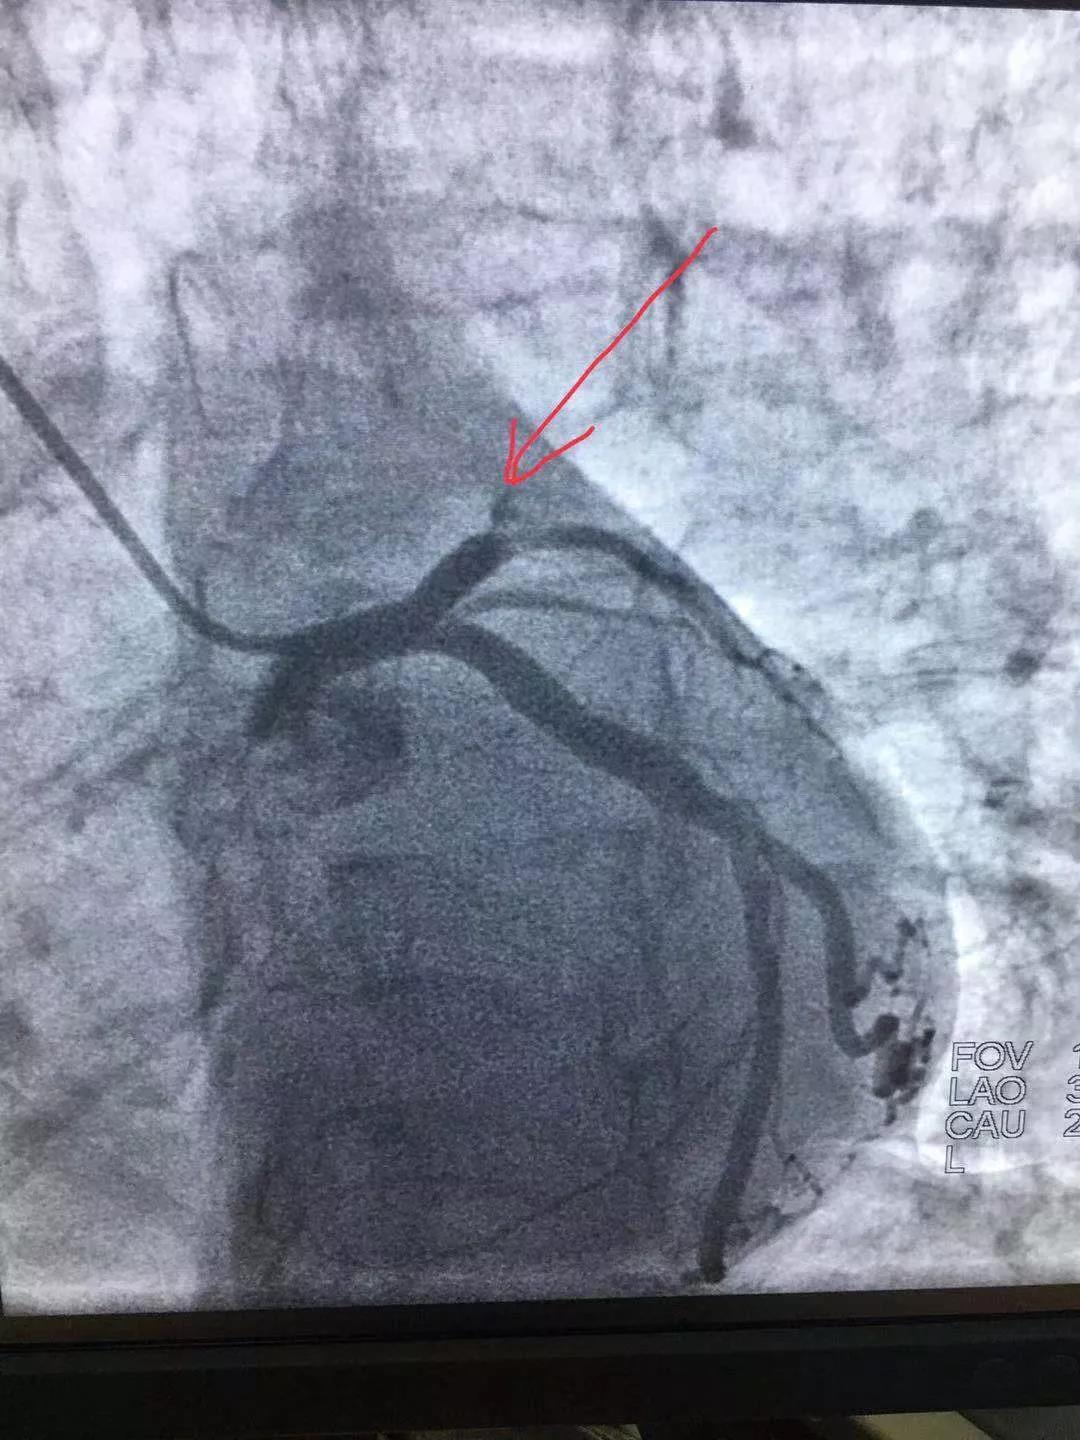

手術(shù)前與手術(shù)后情況

術(shù)中倫主任、徐遵敬副主任發(fā)現(xiàn)病人心臟前降支冠狀動(dòng)脈完全閉塞,征求病人同意后馬上植入支架治療。當(dāng)冠狀動(dòng)脈開通的一煞那,病人胸痛馬上消失,并在手術(shù)臺(tái)上發(fā)出了“我不痛了,我舒服了,你們真是再世華佗”的感嘆。術(shù)后病人曾出現(xiàn)頻發(fā)室性早搏,一過性左束支傳導(dǎo)阻滯,經(jīng)嚴(yán)密治療后病情好轉(zhuǎn)穩(wěn)定。